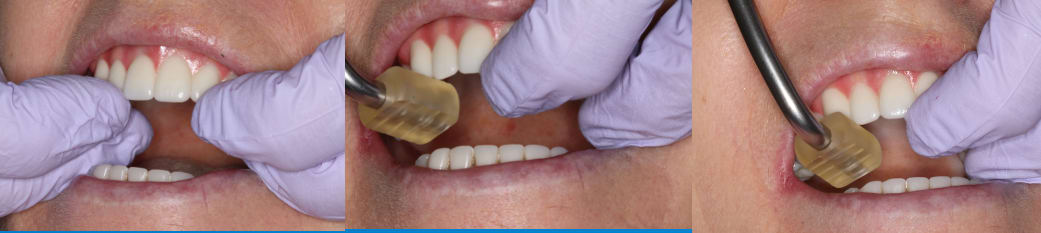

A polymethyl methacrylate (PMMA) appliance was verified for occlusion and esthetics (Figure 10). Once esthetics were evaluated and approved the final LOCATOR FIXED® prosthesis was processed in BruxZir zirconia (Glidewell). The black laboratory procession attachments were removed and replaced with the appropriate final LOCATOR FIXED® insert (Figure 11). The LOCATOR abutments and processing attachments are illustrated in Figure 12, which shows the tools for seating and removing the proprietary inserts and the insertion and removal tools. Proper inserts were selected and positioned per the manufacturer’s instructions (Figure 13). The final zirconia fixed prosthesis was seated using the seating tool and evaluated for stability (Figure 14). The prosthesis allowed for minimal palatal coverage, and the functional and esthetic maxillary reconstruction was complete (Figure 15 and Figure 16).